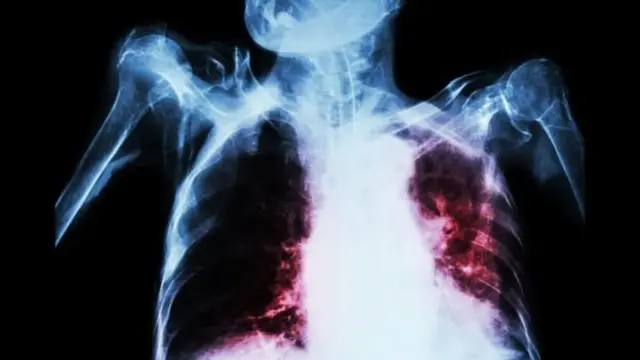

காசநோய் சிகிச்சையில் `புரட்சியை` ஏற்படுத்தும் ஒரு புதிய மருந்தை ஆராய்ச்சியாளர்கள் கண்டறிந்துள்ளனர்.

ஒவ்வொரு வருடமும் 1.5 மில்லியன் மக்களை பலிவாங்கும் காசநோய்க்கு எதிராக ஒரு நீண்ட நாள் பாதுகாப்பை இந்த மருந்து வழங்கும் என நம்பப்படுகிறது.

அதீத தொற்று நோய் ஆன காசநோய், பாக்டீரியாவால் ஏற்படுகிறது. மேலும் தற்போது பயன்பாட்டில் உள்ள ’பிசிஜி ஜாப்’ தடுப்பூசி அவ்வளவு வீரியமாக இல்லை. இருப்பினும், ஆரம்பகட்ட சோதனைகள் வெற்றிகரமாக நிரூபிக்கப்பட்டாலும், தடுப்பூசி உரிமம் பெற இன்னும் சில ஆண்டுகள் ஆகும் என எதிர்பார்க்கப்படுகிறது.